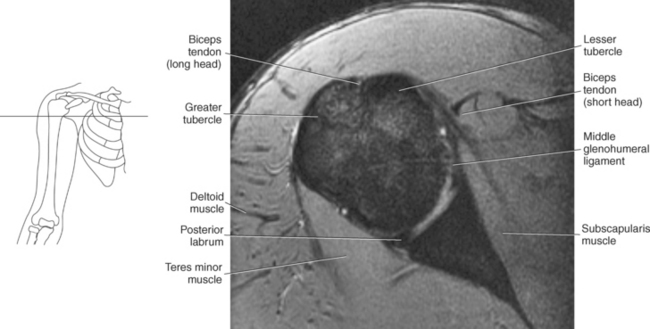

The humerus is a long bone that articulates with the scapula superiorly and the radius and ulna inferiorly. It consists of a body or shaft, a lower end (distal end), and an upper (proximal) end (Figure 9.13). The proximal end is formed by the head of the humerus. Two tubercles project from the humeral head to provide attachment sites for tendons and ligaments. The lesser tubercle is located on the anterior surface of the humeral head, whereas the greater tubercle is located on the lateral surface of the humeral head (Figures 9.12 through 9.15). The tubercles are separated by the intertubercular (bicipital) groove, which is bounded by the crests of the lesser and greater tubercles as it descends the humerus (Figures 9.9 and 9.13 through 9.15). The humerus has two necks, the more proximal anatomic neck and the surgical neck, located inferior to the tubercles just distal to the humeral head (Figures 9.13 and 9.16). In the middle of the body or shaft of the humerus, on the anterior surface, is the roughened area of the deltoid tuberosity that gives attachment for the deltoid muscle (Figure 9.13).

The edge of the glenoid fossa is surrounded by a fibrocartilaginous ring termed the glenoid labrum (glenoid lip) (Figure 9.17). The glenoid labrum is a fold of the articular capsule, which functions to deepen the articular surface of the glenoid fossa. Superiorly, the labrum blends with the long head of the biceps brachii muscle. In cross section it appears triangular (Figure 9.18). The three glenohumeral ligaments (superior middle, and inferior) are thickenings of the fibrous capsule that surrounds the shoulder joint; they contributes to the formation of the glenoid labrum (Figures 9.17 and 9.19). They extend from the supraglenoid tubercle of the scapula to the lesser tubercle of the humerus. Also aiding in strengthening the fibrous capsule is the coracohumeral ligament that passes from the lateral side of the coracoid process of the scapula to the anatomic neck of the humerus (Figure 9.19). The coracoacromial ligament is another important ligament located on the anterior portion of the shoulder. As this ligament joins the coracoid process and acromion, it forms a strong bridge, termed the coracoacromial arch, which protects the humeral head and rotator cuff tendons from direct trauma and prevents displacement of the humeral head superiorly (Figures 9.17 and 9.19). The coracoclavicular ligaments help to maintain the position of the clavicle, in relation to the acromion, by spanning the distance between the clavicle and coracoid process of the scapula (Figure 9.19). The acromioclavicular ligament, at the acromioclavicular joint, provides support for the superior surface of the shoulder (Figures 9.17 and 9.19). The transverse humeral ligament is a broad band of connective tissue passing from the greater tubercle to the lesser tubercle of the humerus, forming a bridge over the intertubercular groove for protection of the long head of the biceps tendon (Figure 9.19). The ligaments of the shoulder are demonstrated in Figures 9.20 through 9.30.

The biceps brachii muscle is located on the anterior surface of the humerus and acts as a strong flexor of the forearm. The biceps brachii muscle is so named “biceps” because of its two expanded heads of proximal attachment (long and short). The tendon of the long head arises from the supraglenoid tubercle and courses through the intertubercular (bicipital) groove to merge with the tendon from the short head. The short head of the biceps brachii muscle originates from the coracoid process and joins with the long head to create the biceps brachii muscle, which terminates in two tendons. The stronger tendon inserts on the radial tuberosity, and the other tendon creates the bicipital aponeurosis, which radiates into the fascia of the forearm (Figure 9.55).